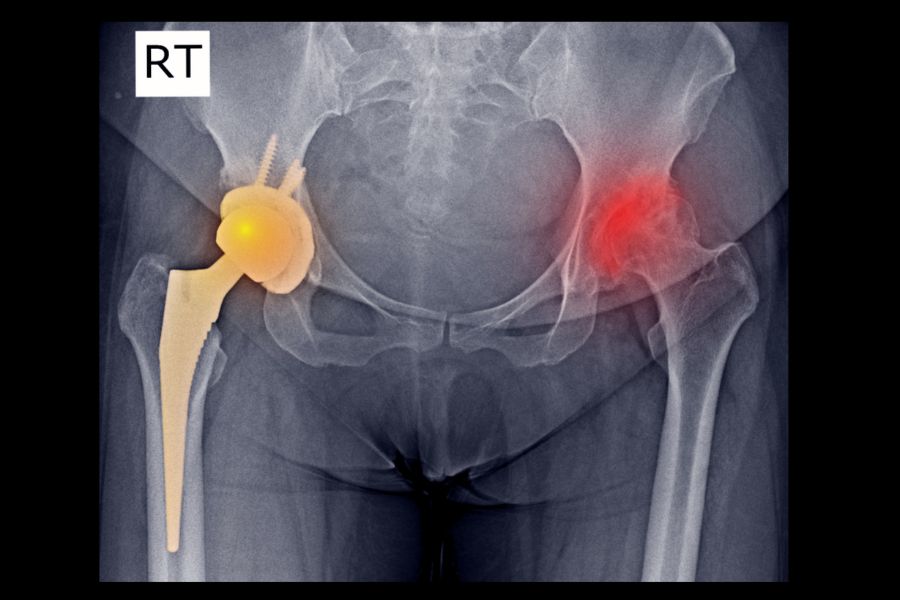

Gelişimsel kalça displazisi (GKD), kalça eklemini oluşturan uyluk kemiği başı (femur başı) ile leğen kemiği üzerindeki yuva (asetabulum) arasındaki ilişkinin bozulduğu bir durumdur. Bu bozulma doğumla birlikte başlayabilir veya doğum sonrası gelişebilir. Kalça yuvasının yeterince derin olmaması ya da eklem bütünlüğünün zayıf olması durumunda, kalça başı yuvasından kısmen çıkabilir (subluksasyon) ya da tamamen çıkar (dislokasyon). Bu durum erken dönemde fark edilip tedavi edilmediğinde ciddi yürüme problemleri ve kalça ağrılarına neden olabilir.

Gelişimsel Kalça Displazisi ve Çıkığı Tedavi Seçenekleri

Tedavi, çocuğun yaşı, kalça çıkığının şiddeti ve hangi aşamada fark edildiğine göre değişir. Erken tanı konulduğunda tedavi süreci oldukça kolay ve etkilidir.

3. Cerrahi Müdahale (18 ay ve üzeri)

Gecikmiş veya ciddi çıkık vakalarında açık cerrahi uygulanır. Cerrahi sonrası kalça yeniden şekillendirilir ve stabilize edilir. Ameliyat sonrası alçı ve fizik tedavi süreçleri gerekebilir.